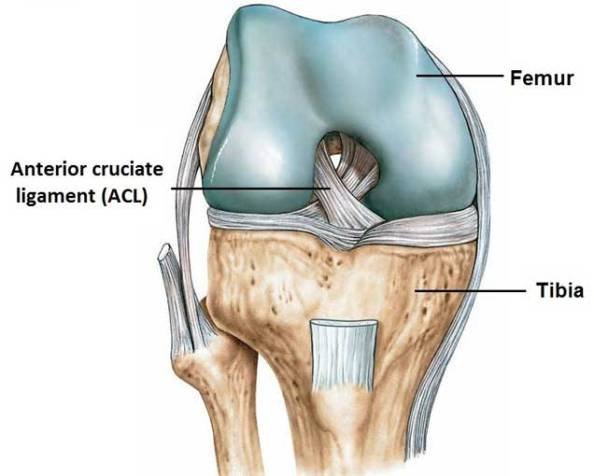

The Anterior Cruciate Ligament (ACL) is a vital structure in the knee that provides stability during activities involving sudden stops, starts, and changes in direction. ACL injuries are relatively common and can range from partial to complete tears. While complete ACL tears often require surgical intervention, partial ACL tears can sometimes be managed successfully without surgery, thanks to innovative treatments like Image-guided Comprehensive Platelet-Rich Plasma (PRP) with Prolotherapy.

The anterior cruciate ligament goes from the back of the top of the knee- the femur, to the front of the bottom of the knee- the tibia.